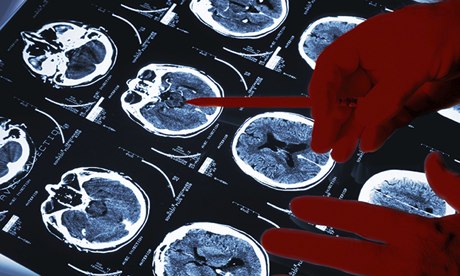

Rates of stroke and subsequent death have dropped in the U.S. over the past two decades, but new research shows that not everyone has made the same gains.

The study, published in the Journal of the American Medical Association, found a 24 percent overall decline in first-time strokes in the past two decades, along with a 20 percent drop per decade in deaths.